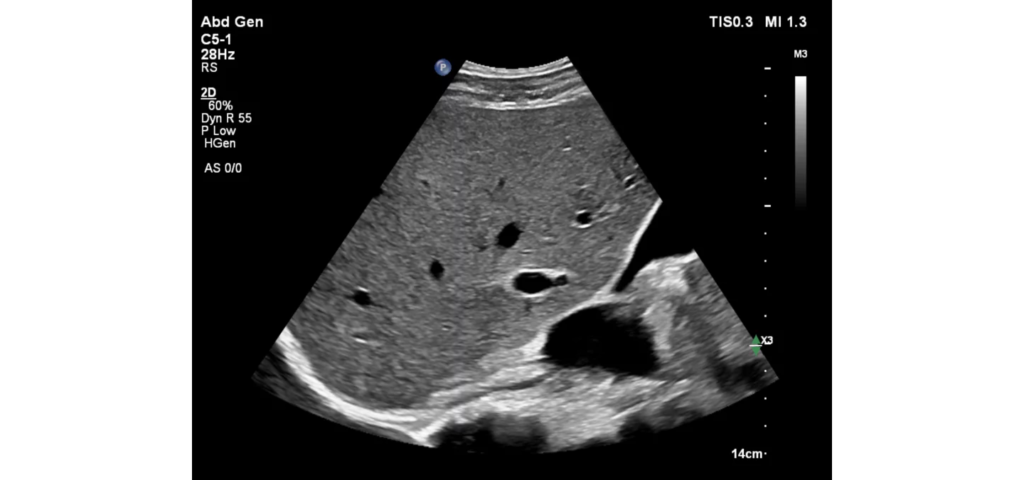

Philips EPIQ Elite ultrasound features an exceptional level of clinical performance, workflow, and advanced intelligence to meet the challenges of today’s most demanding practices. The EPIQ Elite platform brings ultimate solutions to ultrasound, with clinically tailored tools designed to elevate diagnostic confidence to new levels.